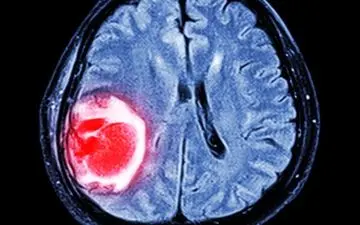

یک مطالعه جدید درباره اینکه آیا امواج تلفن همراه موجب سرطان مغز میشود به پاسخهای قطعی رسیده است.

تاکنون اطلاعات کافی درباره اثرات مخرب تلفن همراه بدست نیامده است، تنها چند نتایج احتمالی درباره سرطان مغز، آسیبهای…